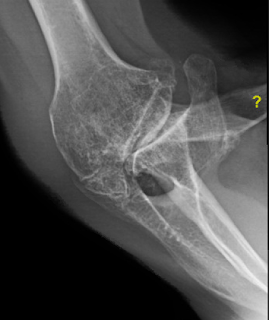

Here are his films at 7 months when he presented requesting the same procedure on the contralateral shoulder for a similar deformity.

On examination he demonstrated 140 degrees of comfortable active elevation.